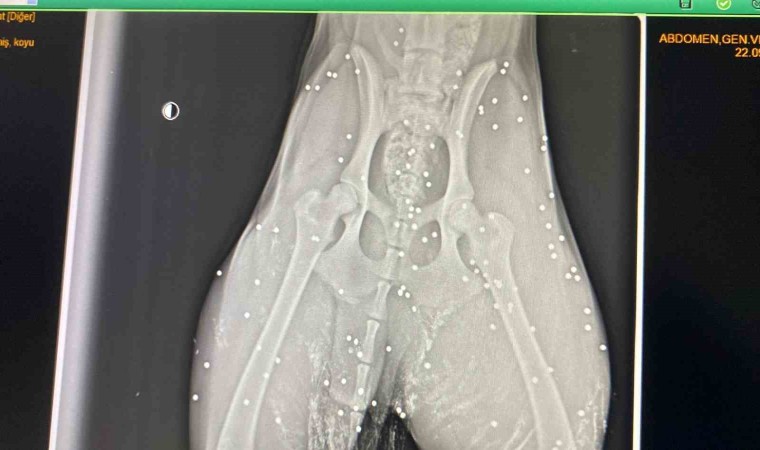

Antalya’nın Aksu ilçesinde silahla vurulan sokak köpeğinin çekilen röntgen görüntüsü adeta şoke etti. Yapılan incelemede köpeğin kalçasında onlarca saçmaya rastlanırken, veterinerde ilk müdahalesi yapılan köpek, bir hayvansever tarafından bakımı üstlenildi.

Olay, Aksu ilçesi Solak Mahallesi Hasan Tahsin Caddesi üzerinde meydana geldi. Alınan bilgiye göre, sokak üzerinde iki el silah sesi duyan Gülhan Tünay, bir süre sonra yanına bir sokak köpeğinin acı içerisinde geldiğini gördü. Tünay’ın ilk incelemesinde sokak köpeğinin üzerinde kan izlerine rastlandı. Köpeğin vurulmuş olabileceği ihtimali üzerinde durarak veterinere götüren Tünay, kalçasından çekilen röntgen görüntüsüyle adeta hayatının şokunu yaşadı. Yapılan incelemede köpek üzerinde onlarca saçmaya rastlandı. İlk müdahalesi ilçede bulunan klinikte Veteriner Hekim Mustafa Gülcü tarafından yapılan sokak köpeği, Tünay tarafından sahiplenilerek eve götürüldü.

Polis ekipleri ise şikayet üzerine harekete geçerek olayla ilgili inceleme başlattı. Köpeğin durumu hakkına açıklama yapan Veteriner Mustafa Gülcü, “Köpek bize silahla yaralanma şikayetiyle geldi. Biz hemen ilk müdahalesini yaptık. Ardından röntgen çektik, incelediğimizde çok sayıda saçmaya rastladık. Yakın mesafeden sıkılsa sinirlerine zarar verebilirdi” sözlerine yer verdi.

“Röntgen görüntülerine baktığımızda köpeğin arka kısmı tamamen yok”

Yaşananları anlatan Gülhan Tünay, “Sabah saatleriydi iki el silah sesi duydum. Ardından köpeği acı içerisinde buldum. Eşime seslenerek eyvah köpeği vurdular dedim. Köpek arka tarafı kanlar içinde geldi. Seçim gecesi de bir köpek vurulmuştu, o köpek şuan ampute oldu. Veterinere söyledim gelip aldılar. Daha sonra polisi aradım ve köpeği vuran kişiden şikâyetçi oldum. Röntgen görüntülerine baktığımızda köpeğin arka kısmı tamamen yok. Kaç tane saçma olduğunu bilmek zor. Şuan durumu çok iyi değil, ilk getirdiğimizde hayati tehlikesi vardı. Şuan serum takılı biz de bekliyoruz. İnşallah özürlü kalmaz. Ne hissettiğini bilmiyorum. İnsanların artık silahlanması önlensin istiyorum” dedi.